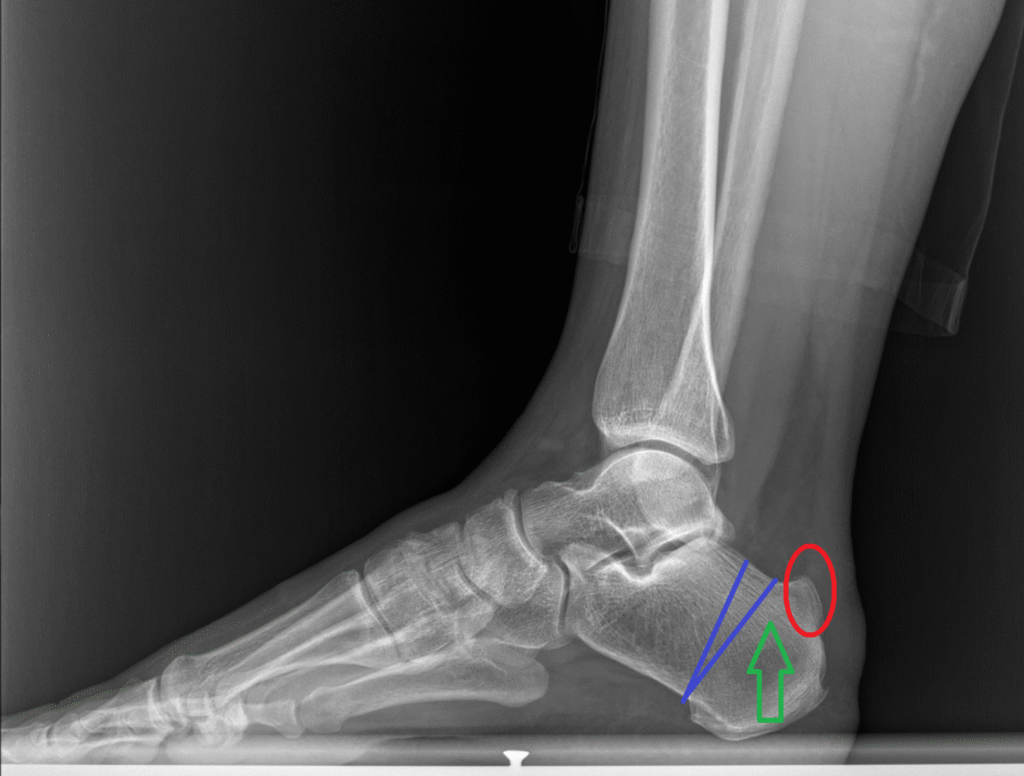

Cerrahi planlama ve osteotomi şeması

- Zadek osteotomisi: Kalkaneusun arka kısmından kama çıkarılarak kemik çıkıntısı düzeltildi.